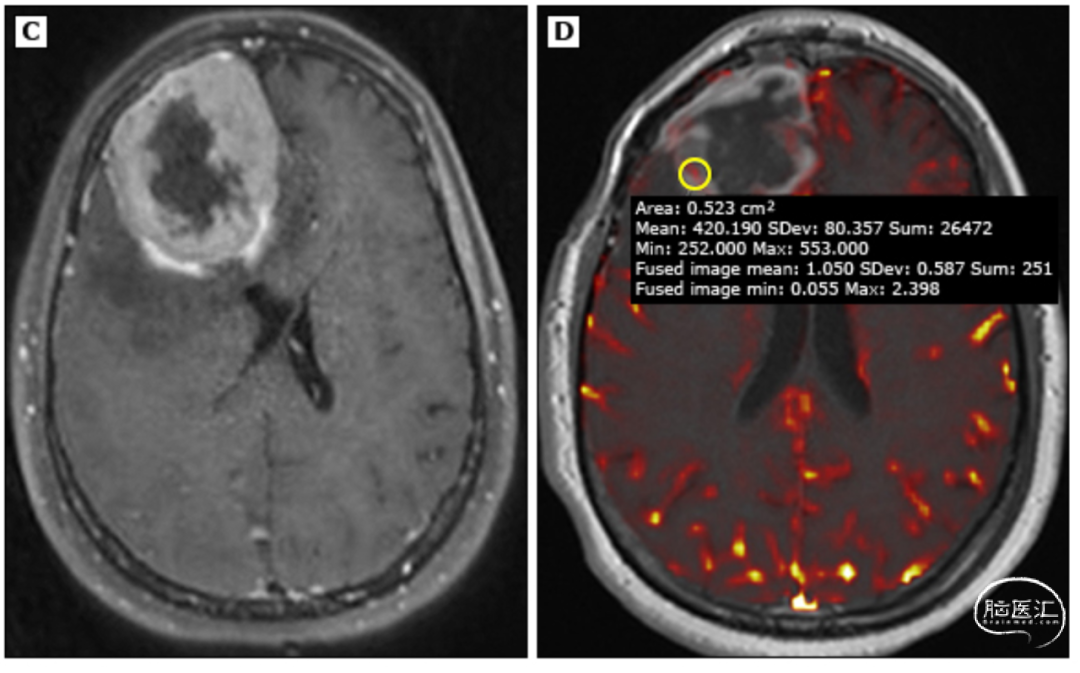

在实际操作中,光靠神经影像学检查,想要区分良性脑膜瘤和那些坏家伙——非典型或恶性脑膜瘤,是真的挺不容易的。

与非典型脑膜瘤患者相比,恶性脑膜瘤患者需要更密切的放射影像学监测:通常在初始治疗后3~5年每3~6个月复查1次MRI,之后每6~12个月复查1次。